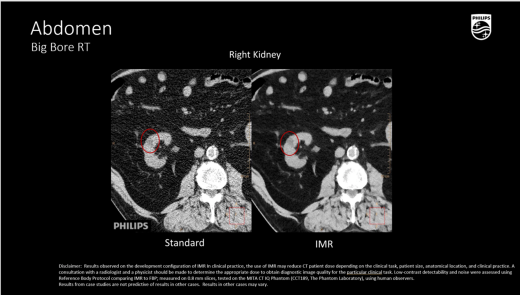

Абдоминальная и тазовая локализация

- Визуализация мягкотканных опухолей (печень, почка, поджелудочная железа, органы таза) с контурированием OAR,

O-MAR (Orthopedic Metal Artifact Reduction)

- Комплексный алгоритм для снижения артефактов от эндопротезов, спиц, хирургических скоб и зондов,

- Существенно повышает точность КТ-контурирования в условиях металлоиндуцированных искажений, что критично для радиотерапии позвоночника и малого таза.